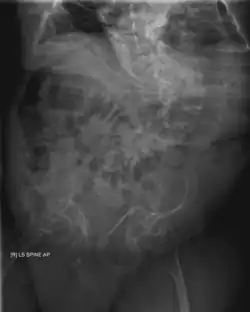

Spine, chest, and pelvis

Four X-rays of a 24-year-old American man (Fredrick Brennan), who had had more than one hundred bone fractures in his lifetime, and received a childhood clinical diagnosis of type IV–B OI. Genetic diagnosis in 2018 identified a previously uncatalogued pathogenic variant in the gene which encodes proα2(I) chains of type I procollagen, COL1A2, at exon 19, substitution c.974G>A. Due to childhood neglect and poverty, Brennan never received surgery to implant intramedullary rods. Malunions are evident as the humerus and femur were broken in adolescence, but orthopedic care did not follow. Severe scoliosis, as well as kyphosis, are also evident. The unavoidably low contrast in the film is due to a combination of Brennan's obesity and low bone mineral density (BMD). His BMD Z-score was -4.1 according to results of a dual-energy X-ray absorptiometry (DXA) scan also done in 2018.